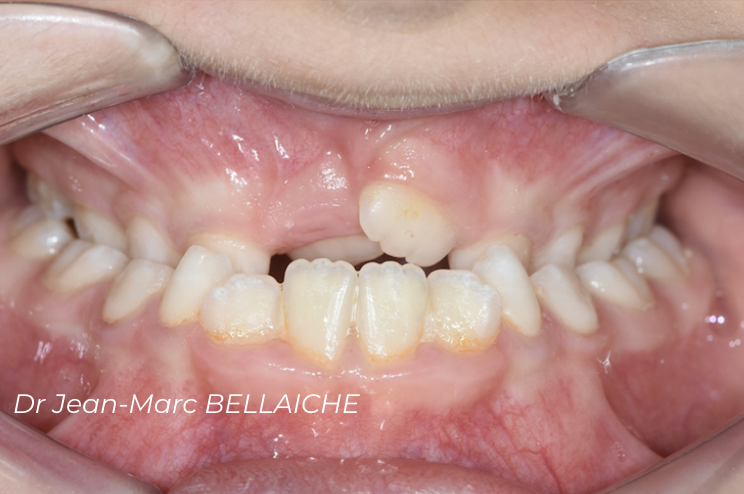

Cas 7 : Classe II avec encombrement sévère – Traitement sans extraction

Situation "Avant Traitement" : Classe II dentaire associée à un encombrement important de l’arcade supérieure, avec canines enclavées.

Cette jeune patiente présentait un très gros encombrement au maxillaire, rendant l’éruption des canines difficile. Après un diagnostic complet (photos, empreintes 3D, radio, examen du visage et endobuccal), un traitement sans extraction a été choisi. L’objectif était de mettre en place les canines tout en préservant l’équilibre des arcades. Un exemple de traitement conservateur possible même en présence d’un encombrement marqué.